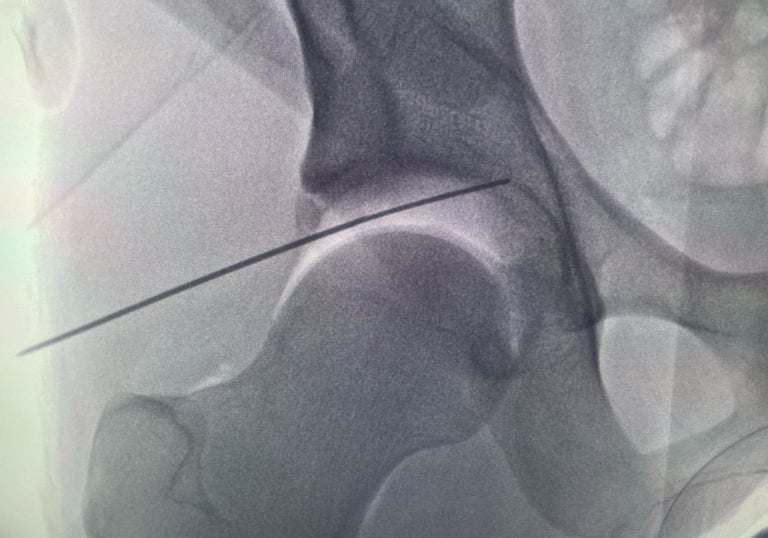

Galería Médica

Imágenes de procedimientos y técnicas en cirugía de cadera.